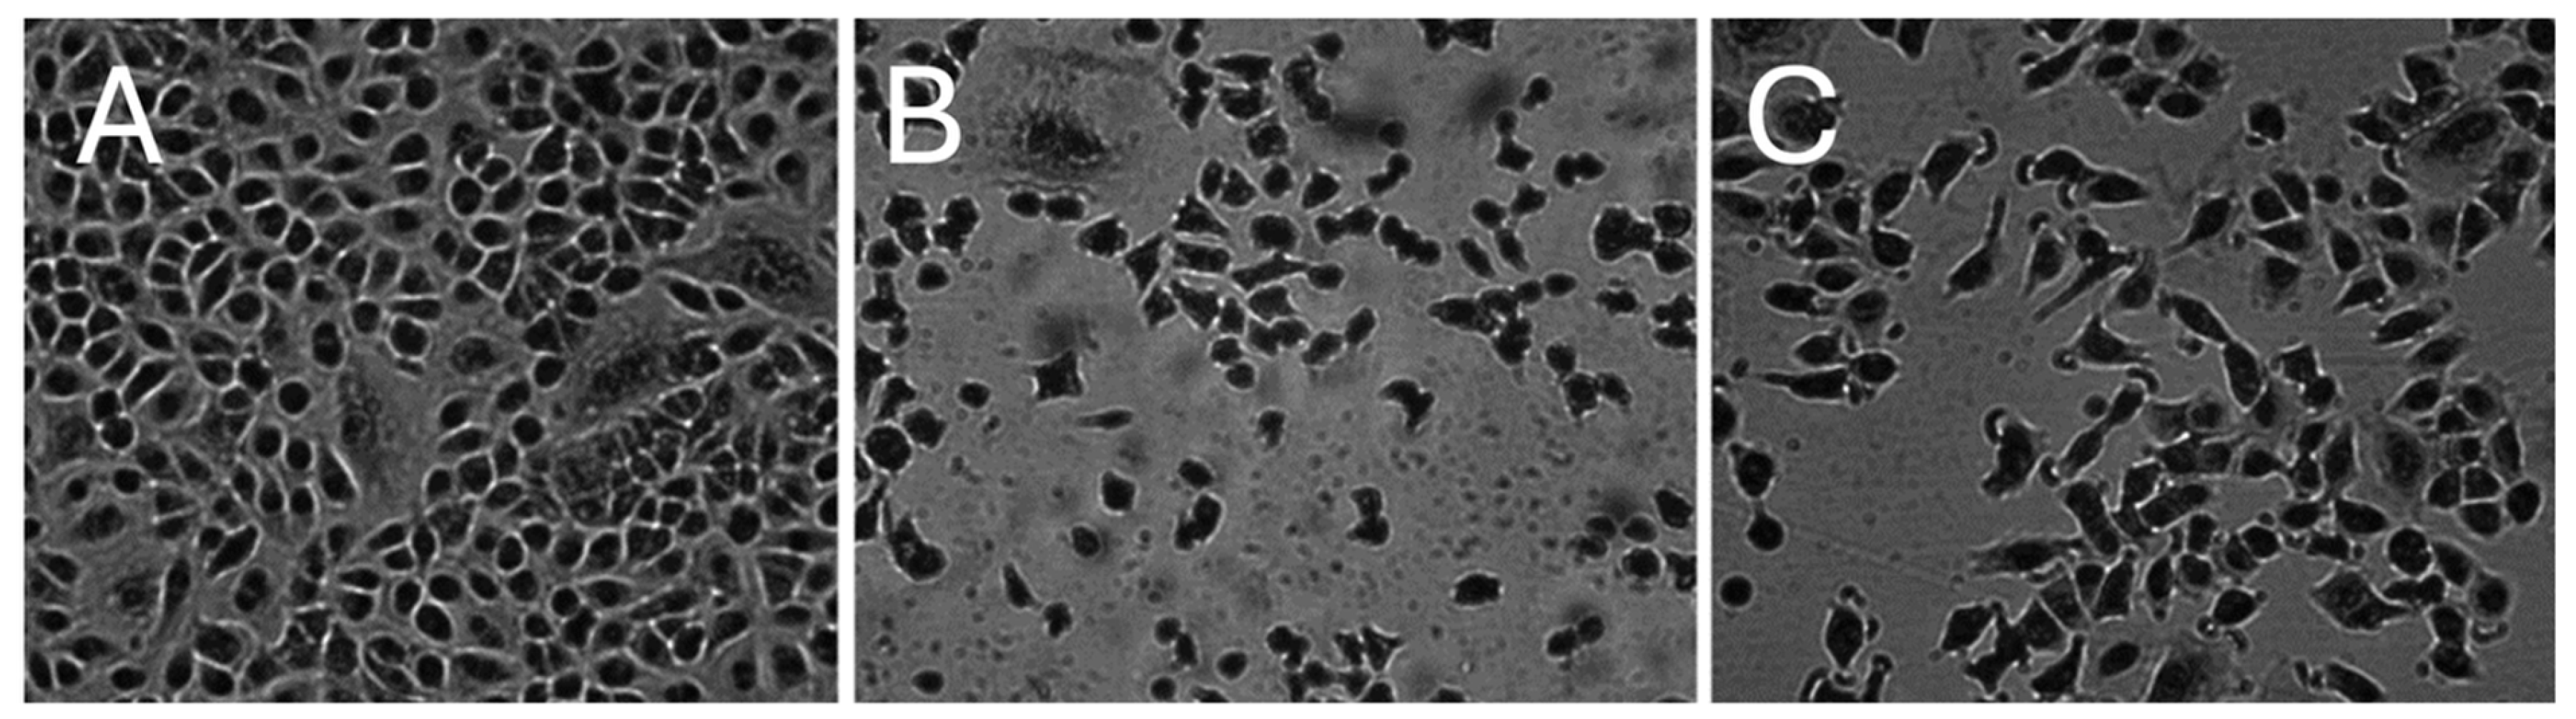

2.1.1. Morphology of A549 Cells

4.5. Microscopy and Cell Morphology